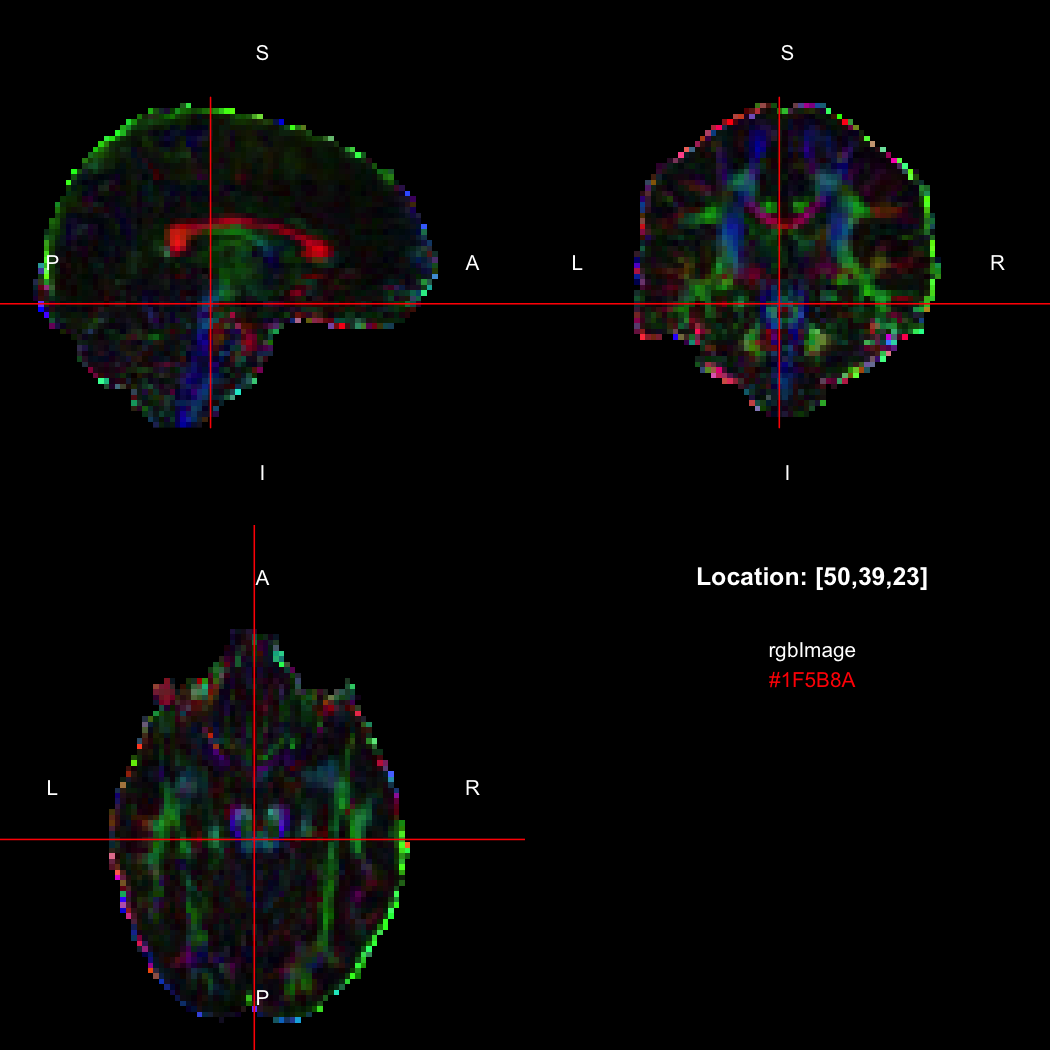

R’s native representation for RGB values is CSS-style hex strings of character mode, which are reasonably space-efficient (8 or 10 bytes per value) but a little clunky to work with. For efficiency of interchange between R and the NIfTI-internal datatypes, RNifti uses a byte-packed representation of integer mode instead, which takes up 4 bytes per value. Of course, the viewer understands this format.

rgbImage <- readNifti(system.file("extdata", "example_rgb.nii.gz", package="RNifti"))

print(rgbImage)

## Image array of mode "integer" (2.1 Mb)

## - 96 x 96 x 60 voxels

## - 2.5 x 2.5 x 2.5 mm per voxel

class(rgbImage)

## [1] "niftiImage" "rgbArray"   "array"

view(rgbImage)

plot of chunk unnamed-chunk-15

Notice that values are shown in the viewer using R’s conventional hex string format, but the data is of class rgbArray. The function of the same name can be used to create these arrays from strings or channel values, for the purposes of building RGB images from data, while the as.character method and channels function perform the opposite conversions.

as.character(rgbImage, flatten=FALSE)[50,39,23]

## [1] "#1F5B8A"